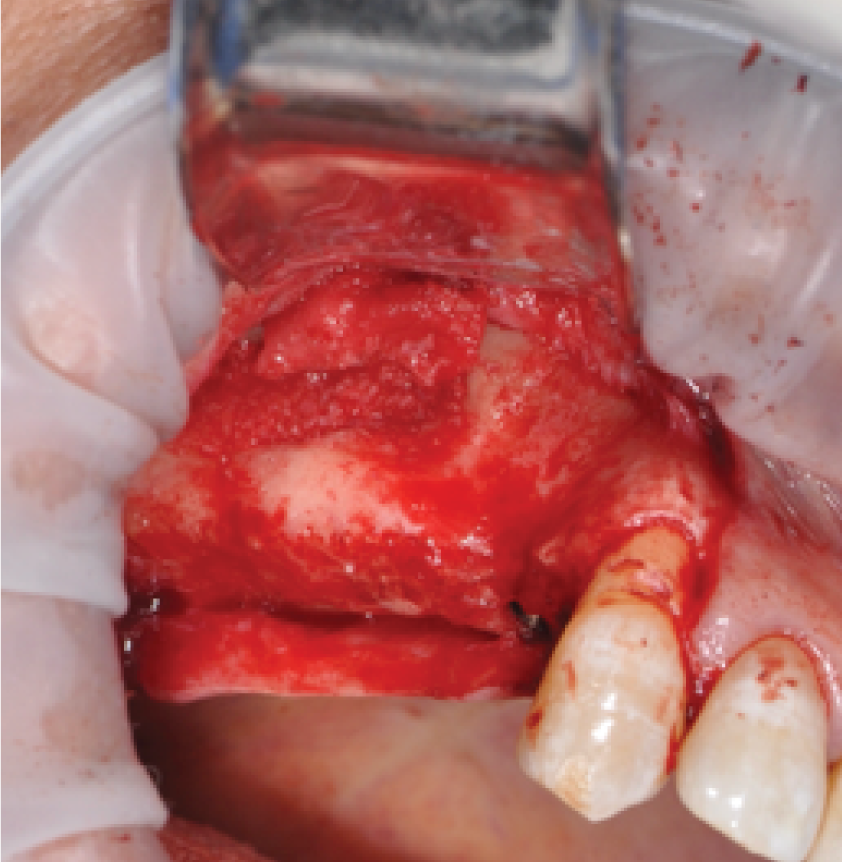

Director’s Clinical Cases

Director’s Clinical Cases